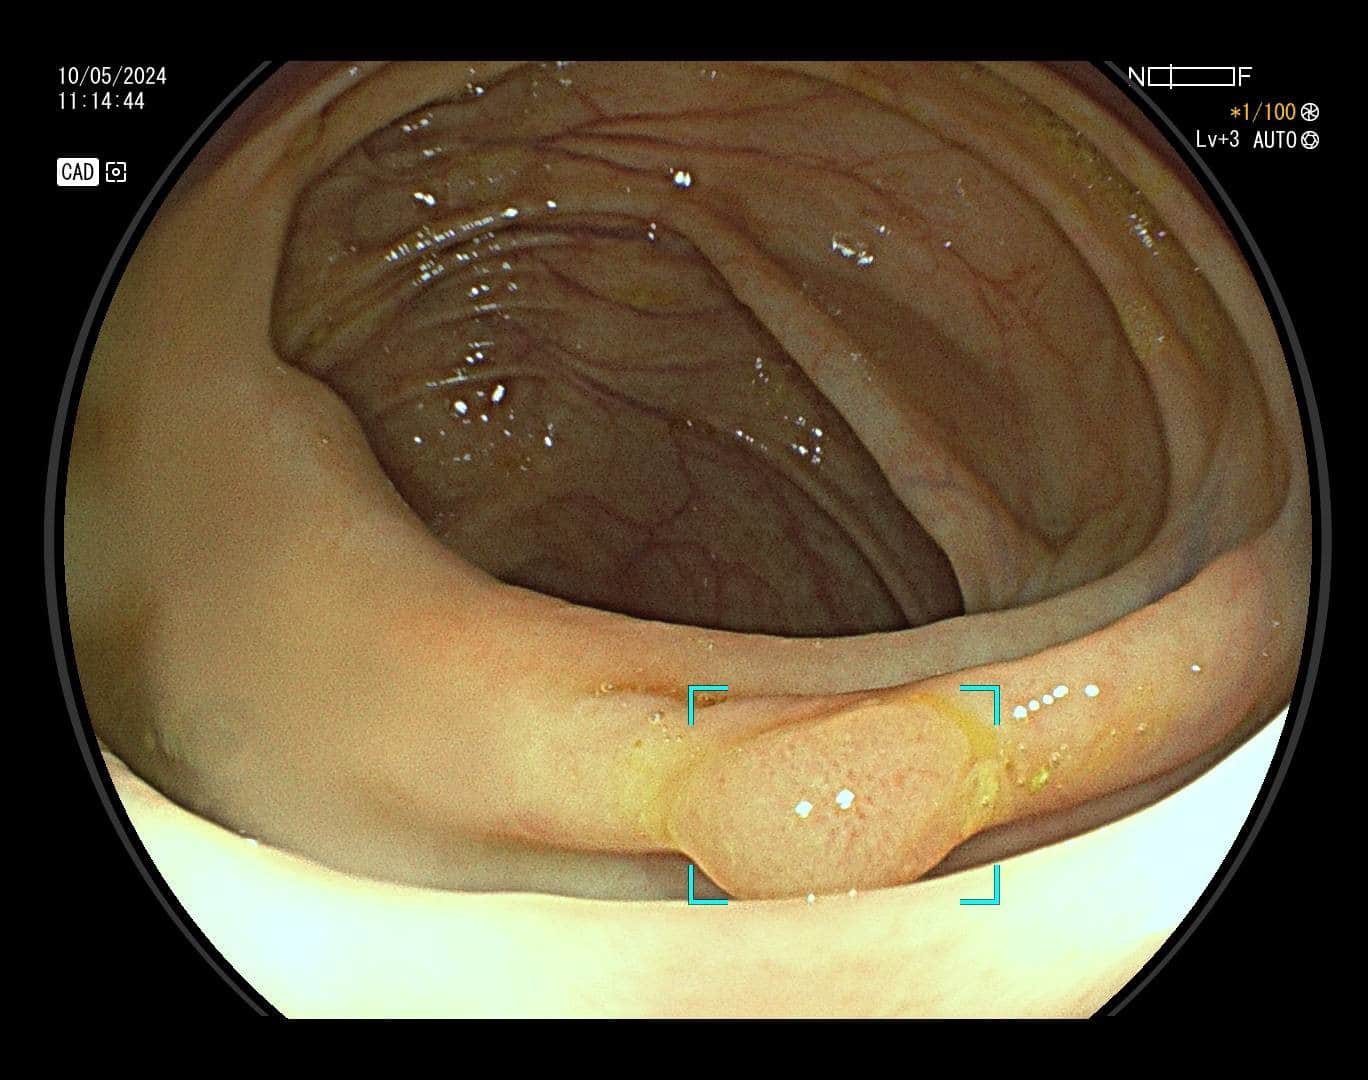

Karcinom debelog crijeva, prema podacima Hrvatskog registra za rak, drugi je po učestalosti uzrok maligne bolesti u žena, a treći u muškaraca. Ova vrsta raka razvija se iz polipa, malih izraslina na sluznici debelog crijeva koje nastaju pod utjecajem okolišnih i/ili genetskih čimbenika. S vremenom polip raste, stanice nakupljaju mutacije, te u konačnici dolazi do razvoja karcinoma. Na sreću, nemaju svi polipi zloćudni potencijal. Kod polipa visokog rizika proces do maligne transformacije je najčešće dugotrajan što nam daje priliku za preventivnim djelovanjem – preventivnu kolonoskopiju preporučuje se učiniti s navršenih 50 godina života, a u slučaju obiteljske sklonosti i u ranijoj životnoj dobi. Cilj pretrage nije dijagnosticirati karcinom već pravovremeno detektirati i ukloniti njegov predstadij – polip.

Kako bi pregled debelog crijeva bio temeljit potrebna je dobra priprema crijeva (očišćenost), no mali i plitki polipi, unatoč optimalnim uvjetima pretrage mogu ostati nezamijećeni, a zbog anatomije crijeva i skriveni iza nabora.